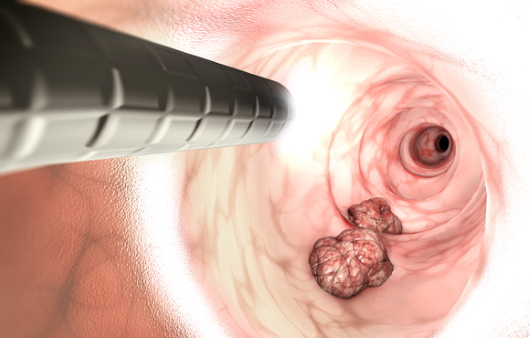

대장내시경은 대장암을 90% 이상 선별하는 방법으로 알려져 있어요. 대장 내시경 검사 시 실제로 암이 발견되면 정밀 검사를 받아야 해요. 먼저 정확한 진단을 받기 위하는 것은 대장내시경 전 식품 유의사항을 정확히 지키는게 중요해요. 식품 유의사항을 잘 지켰다면 병원을 방문하여 검사를 받게 되는데, 검사 시 편한 옷을 갈아입고, 왼쪽 방향으로 옆으로 누운 다음 무릎을 구부린 자세를 취해요. 그다음은 수면 내시경으로 진행한다면 진정제를 투입하면 잠이 들면 항문을 통해 의료 내시경을 삽입하여 검사를 하게 되어요. 비수면의 경우 내시경 삽입 시 강력한 힘이나 말을 하게 되면 삽입이 어려울 수 있기 때문에 긴장을 가능한 한 풀고 진행하게 되어요. 검사 시간은 환자에 따라 조금씩 다르지만 20-30분 정도 소요된다고 해요.

대장내시경 검사 후 나이에 상관없이 고위험군은 3년 후, 저위험군은 5년 후 검사를 권고해요. 대장용종에서 대장암까지의 발병 기간은 5 ~ 10년 이므로 적어도 5~10년 간격으로 재검사는 필수로 필요해요.

하지만 본인의 인체는 본인이 챙겨야 하기에 위암이나 대장암 가족력이 있는 경우 그보다 일찍 정기 검진을 받는게 좋으며 이유할 수 없는 체중 감소, 식욕 부진, 배변, 메스꺼움 중 검은색 또는 묽은 변이 나타나면 진단을 위해 대장 내시경 검사를 권장하며 내시경 치료가 즉시 가능하기에 질병의 조기 발견이 중요해요.